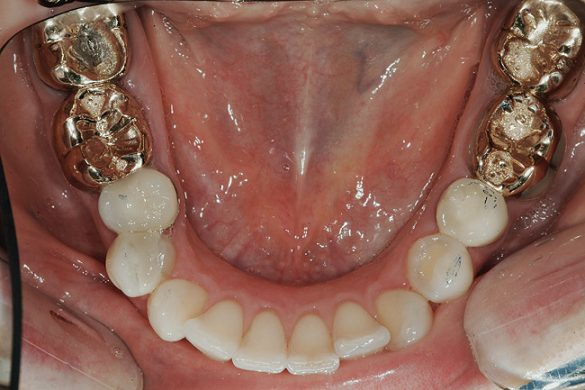

FUNCŢIONAL: La majoritatea dinţilor posteriori ai pacientei ce erau restauraţi cu coroane (fig. 6, 7) era importantă interpretarea minuţioasă a istoricului pacientei şi a rezultatelor evaluării ocluzale. Coroanele din aur de la nivelul 1.7. şi 1.4. prezentau orificii de uzură pe suprafeţele ocluzale, cu semne de minimă uzură pe celelalte coroane posterioare şi la dentiţia naturală. Era evidentă o uzură moderată pe coroana din aur a molarului 4.7.

Traumatismul ocluzal primar s-a observat la dinţii 1.5. şi 2.5. În intercuspidare maximă, s-a notat ocluzie deschisă la segmentele dentare frontale 1.3.-2.3. şi 3.3.-4.3. Dinţii 1.6. şi 4.6., precum şi 2.6. şi 3.6. erau în angrenaj invers (fig. 5, 8). Pacienta prezenta o ocluzie Angle Clasa I. Având în vedere rezultatele istoricului şi examinării s-a stabilit un diagnostic de disfuncţie ocluzală.

ETAPA aIV-a: RESTAURĂRI MANDIBULARE

S-au finalizat restaurările mandibulare cu utilizarea coroanelor integral ceramice din disilicat de litiu pe dinţii 3.7.-3.5., 4.5. şi 4.6., precum şi o restaurare din compozit a dintelui 3.4. Mai întâi s-a restaurat partea stângă, apoi partea dreaptă a pacientei. La restaurarea fiecărui cadran inferior, s-a folosit deprogramatorul Kois ca punct de referinţă stabil şi repetabil în gestionarea ocluziei.